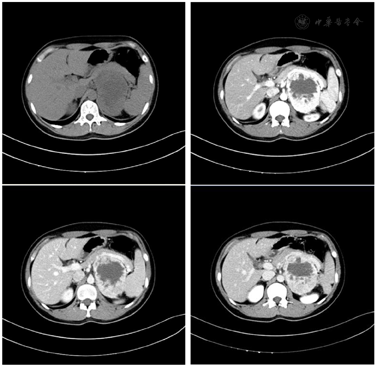

胸腹盆增强CT:左侧肾上腺区可见一巨大肿物影,边界清晰,大小约9.7×5.9cm,平扫中心呈稍低密度,边缘呈等密度,增强扫描动脉期边缘明显强化,静脉期及延迟期持续强化,中心可见片状无强化区,左侧肾上腺正常结构未见显示,脾静脉、胰腺受压向前移位,左肾受压向后移位。腹膜后未见明显肿大淋巴结。左侧肾上腺区病变,嗜铬细胞瘤可能大,建议内分泌科进一步就诊;肝内多发小囊肿;副脾;子宫强化欠均匀,请结合临床;双侧附件区囊性结节,考虑卵巢生理性改变可能(见图1)。

患者,女性,32岁,已婚,职业律师。主诉:诊断宫颈癌发现腹膜后肿瘤1个月。患者于2019年3月出现一次同房后阴道出血,量不多。进一步到当地医院妇科门诊检查:行HPV检测,HPV16(+)。TCT检查:子宫颈鳞状上皮内病变,不除外鳞状细胞癌。妇科B超:子宫内膜点状强回声0.2cm。到我院妇科进一步检查,阴道微生物核酸检测:Trichomonas阴性(-),Gardnerella阴性(-),Candida阴性(-)。鳞状细胞癌抗原(SCCAg):SCCAg 1.0ng/ml。于2019年4月26日我院妇科行阴道镜+宫颈活检,病理结果:(宫颈3°、4°、6°、9°及宫颈管)CIN Ⅱ~Ⅲ,累腺其中(3°、4°)不除外局灶浸润。于2019年5月27日我院妇科行宫颈锥切术,术后病理:(1°~12°)CIN Ⅲ/CIS,其中(1°~11°)可见间质浸润(高分化鳞癌,最深4mm,最宽8mm),距(4)底切缘最近距离1mm,未见明确脉管瘤栓,(4°)距内口切缘<1mm可见CIS,余各切缘未见特殊。拟行妇科宫颈癌根治术,于2019年6月术前行腹盆腔增强CT检查:左侧肾上腺区可见一巨大肿物影,边界清晰,大小约9.7×5.9cm,平扫中心呈稍低密度,边缘呈等密度,增强扫描动脉期边缘明显强化,静脉期及延迟期持续强化,中心可见片状无强化区,左侧肾上腺正常结构未见显示,脾静脉、胰腺受压向前移位,左肾受压向后移位。诊断意见:左侧肾上腺区病变,嗜铬细胞瘤可能大。进一步到泌尿外科门诊完善相关检查后,并药物准备后收入泌尿外科。